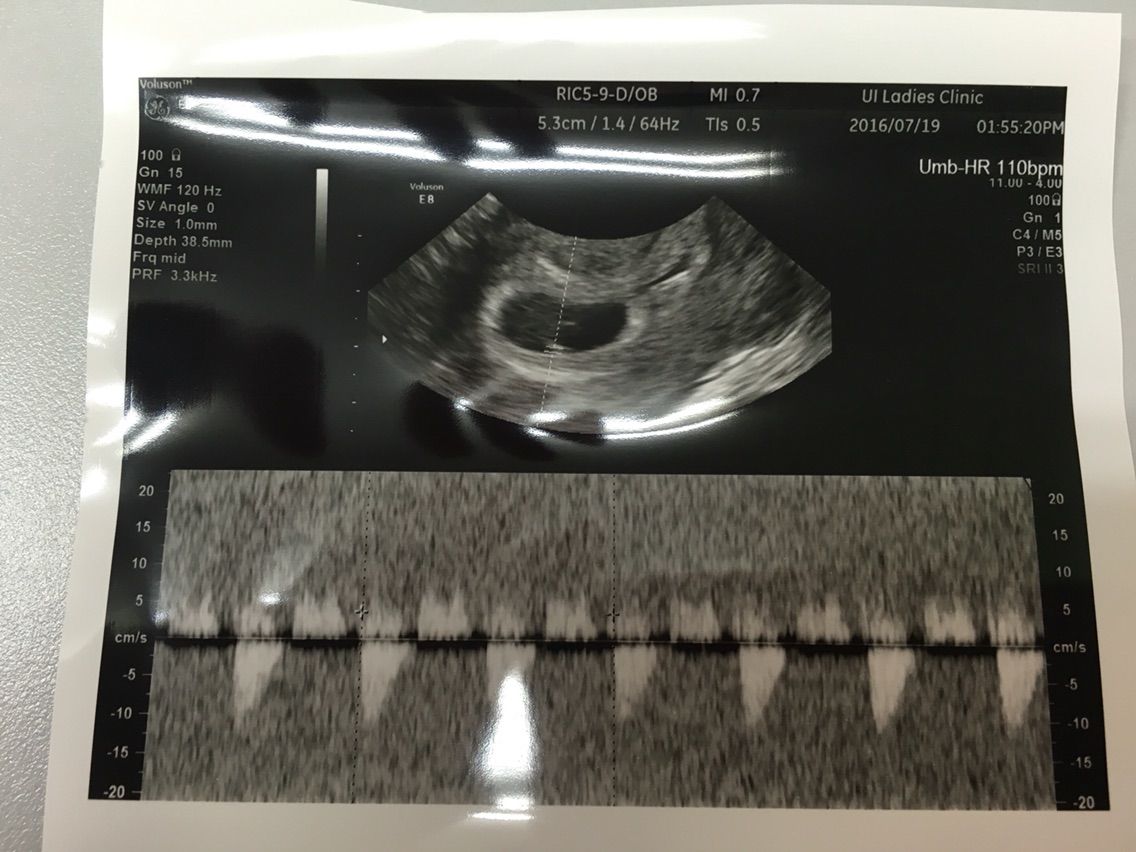

妊娠6週1日 6w1d の超音波 エコー 写真

妊娠6w1dのエコー写真 ページ3